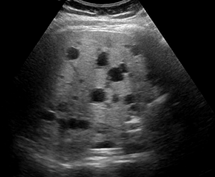

1) 초음파

가장 흔하게 사용되는 검사는 초음파로 간낭종 내부의 상태와 크기를 쉽게 확인할 수 있습니다. 검사 중에 방사선 노출의 위험이 없고, 쉽게 휴대할 수 있어 검진에 많이 사용되고 있습니다.

일반적으로 낭종은 단순한 물집 형태로 나타나기 때문에 초음파 검사 후 추가 검사를 하지 않는 경우가 대부분입니다. 그러나 간혹 간낭종이 개수가 지나치게 많아지는 경우 유전적인 질환과 관련될 수 있습니다.

그중 다낭성 간질환은 간에 수많은 낭종이 생기는 병인데, 다낭성 신질환과 연관되어 나타납니다. 상염색체 우성으로 유전되기 때문에 가족 중에 비슷한 경우가 있는지 살펴보는 것이 좋습니다.